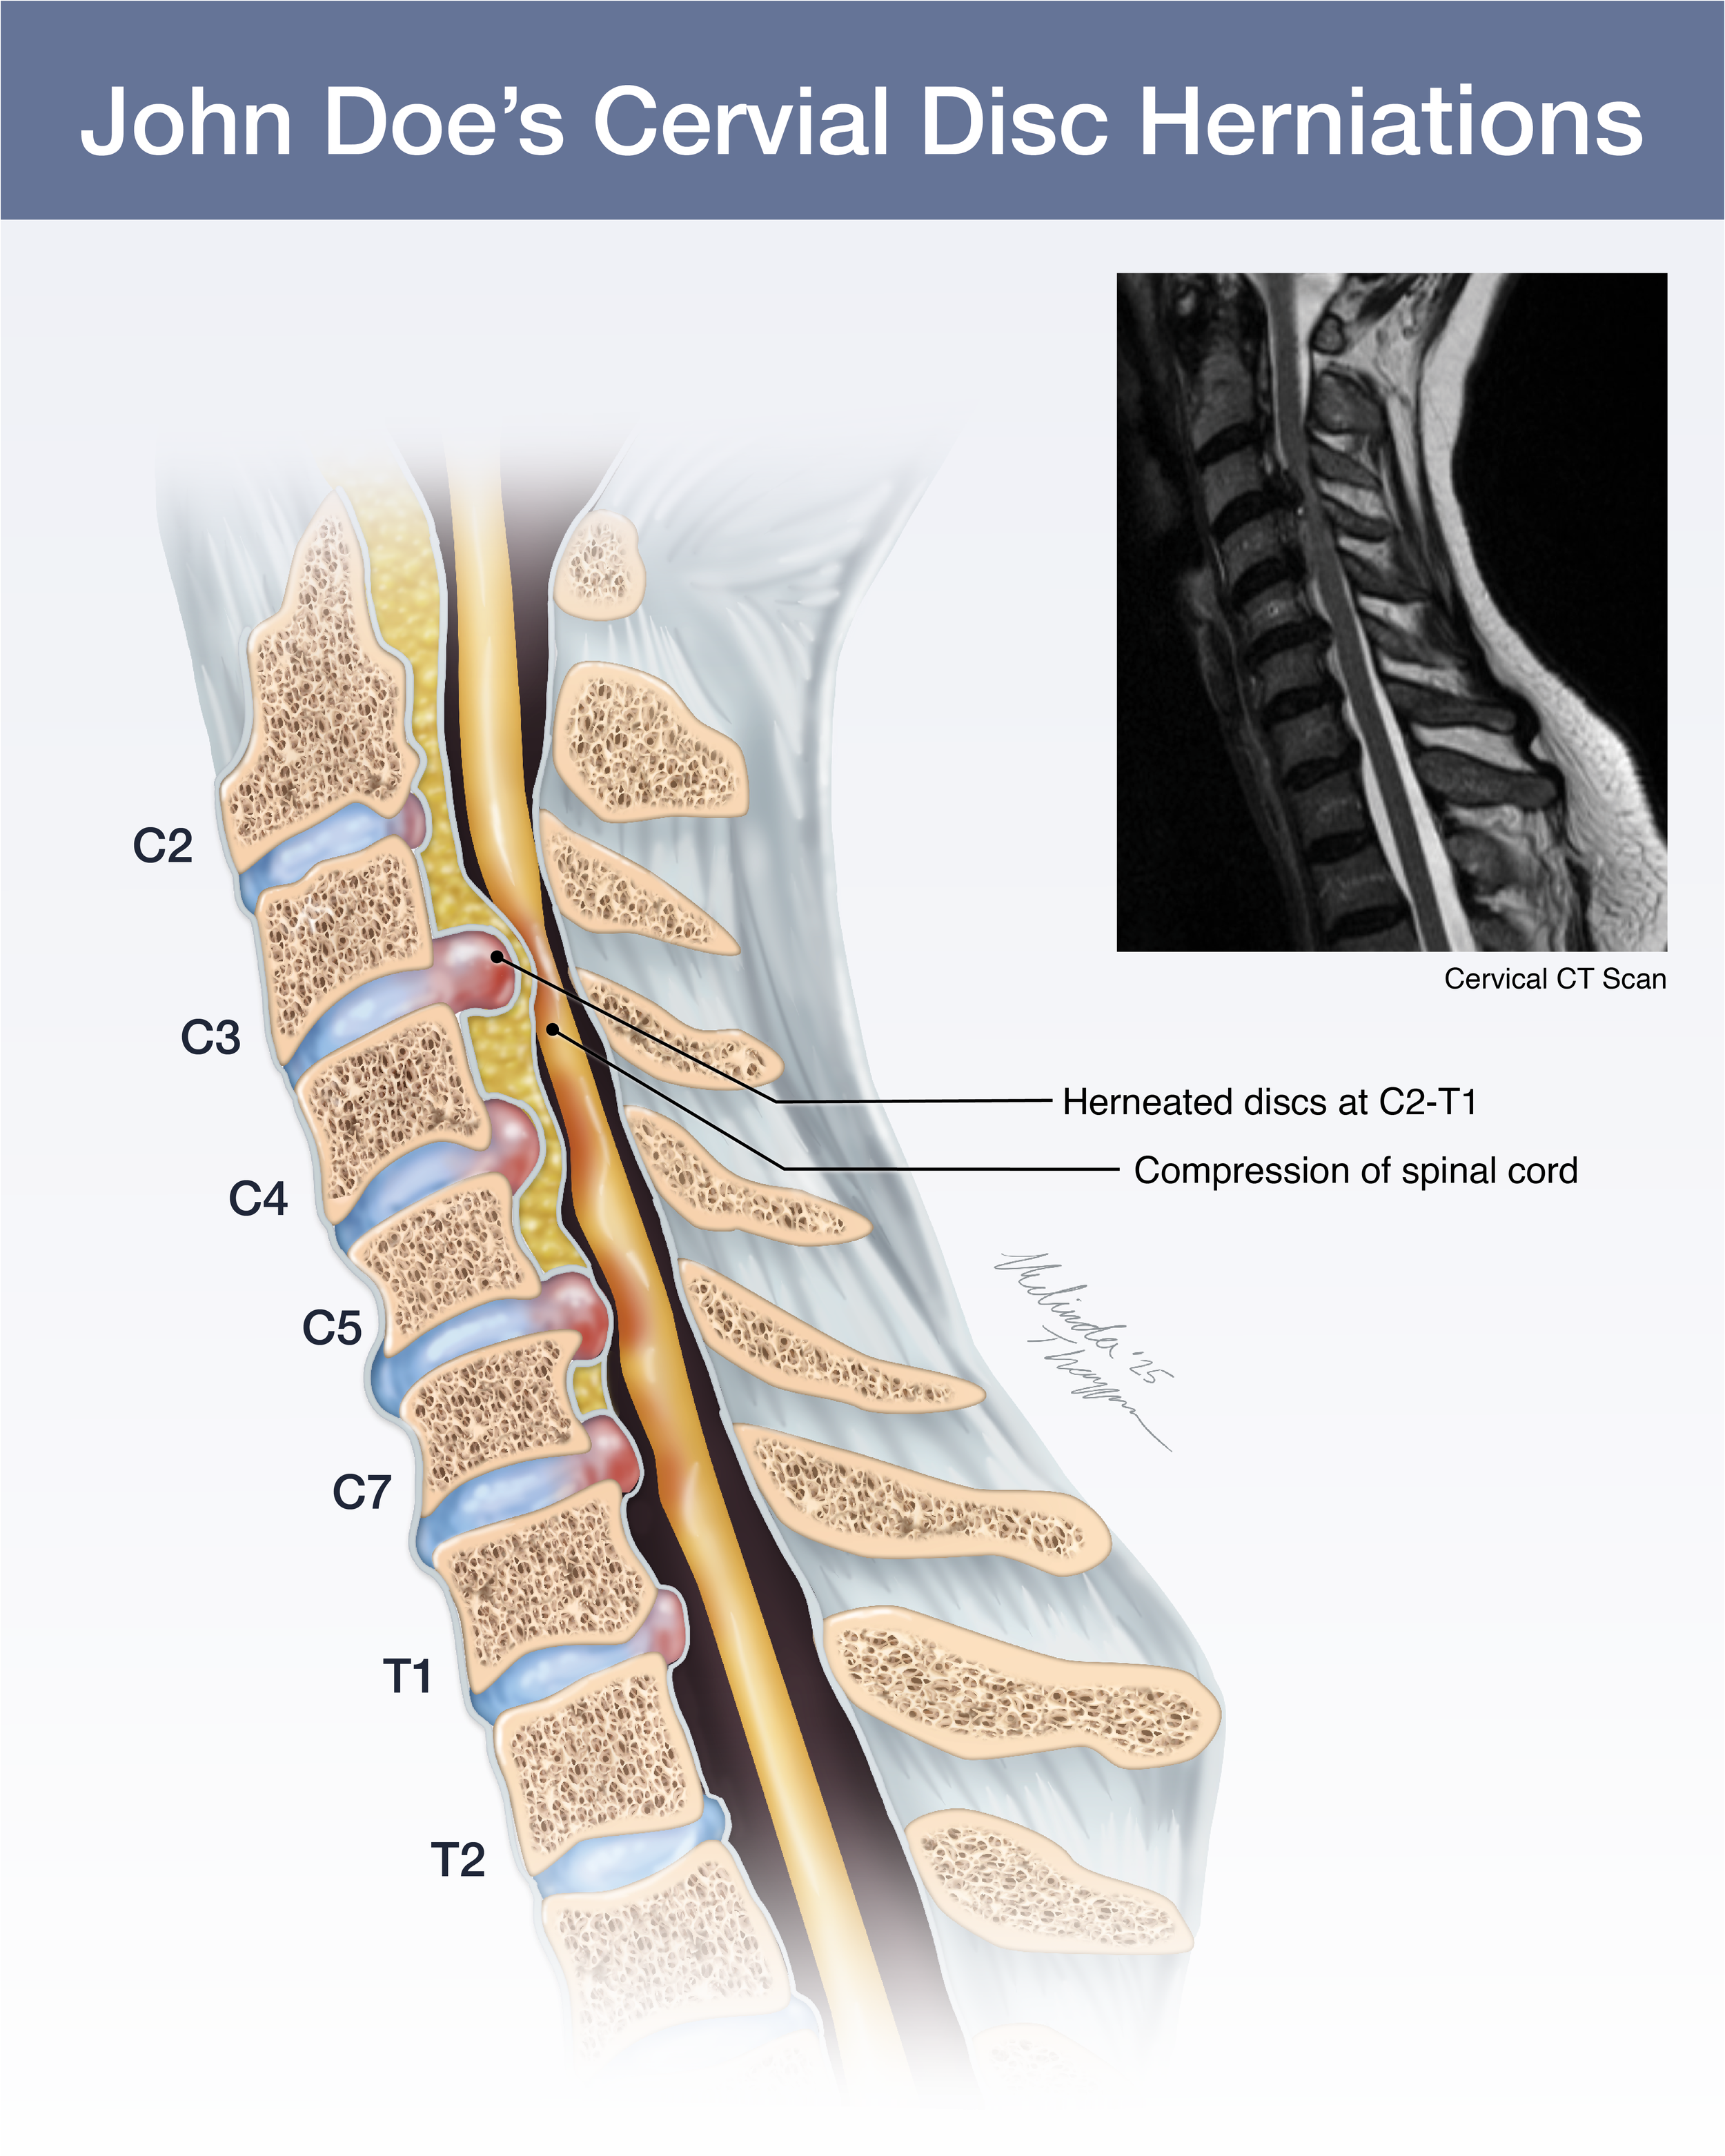

Medical Legal Illustration

Medical Illustration is important in the courtroom for many reasons including communicating scientific information for a lay audience, highlighting injury or anatomical differences, or simply representing potentially disturbing images in a more digestible way. Legal illustrations must be accurate, but still serve to help tell the defendant or plaintiff’s story.

Additional Medical Legal Illustrations

Cervical Disc Herniation: CT Scan Illustration